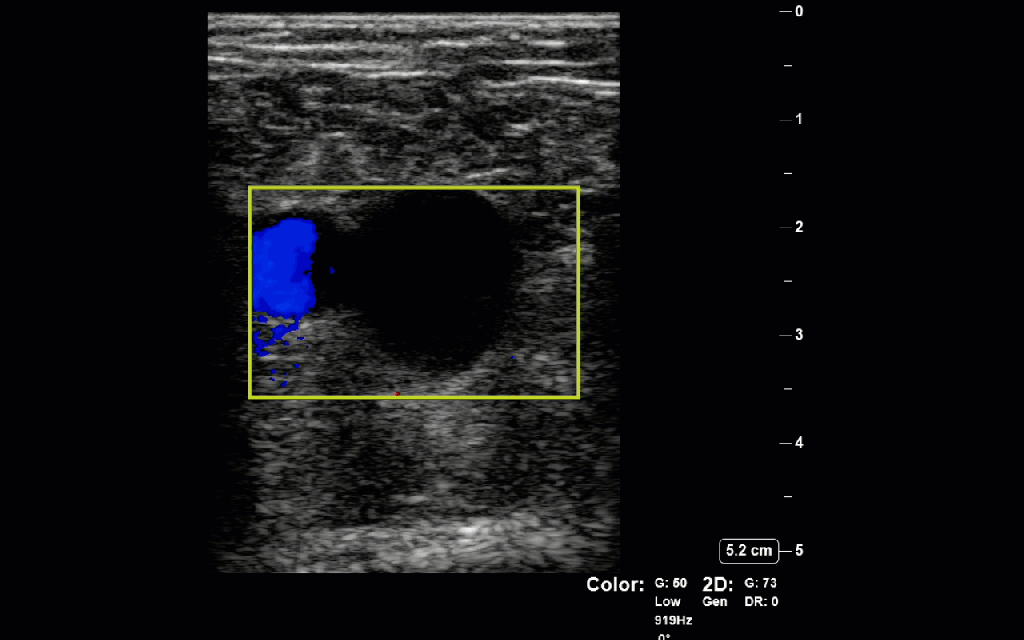

Colour Doppler: The use of colour Doppler can be a helpful adjunctive maneuver for a challenging scan. If there is slow continuous colour signal within the lumen of the vein a clot is less likley, in plane example of the this is shown in the image on the left where low velocity colour is seen occupying the lumen of the common femoral vein (vessel on the right). In the image below a side by side comparison of B-mode and colour doppler of a clot at the branch point of the femoral and deep femoral vein. In this case of clot there is absent signal within the clot and swirling turbulent flow around the edges of the clot due to the intermittent occlusion of part of the vessel wall as the clot floats back and forth in the lumen. But beware, Doppler signal is extremely dependent on being sufficiently parallel to flow, having the Nyquist limit (max/min velocities of the color scale), and gain all set appropriately so proceed with caution when using this as a rule in tool.

Baker’s Cysts: A Baker’s cyst forms in the popliteal fossa from an accumulation/extrusion from the synovial capsule of the knee and can be a false positive for DVT as they are anechoic and non-compressible. In the image on the left the anechoic structure within the Doppler box is a Baker’s cyst. Similar to lymph nodes they are not continuous with surrounding vasculature and have discrete rounded edges.